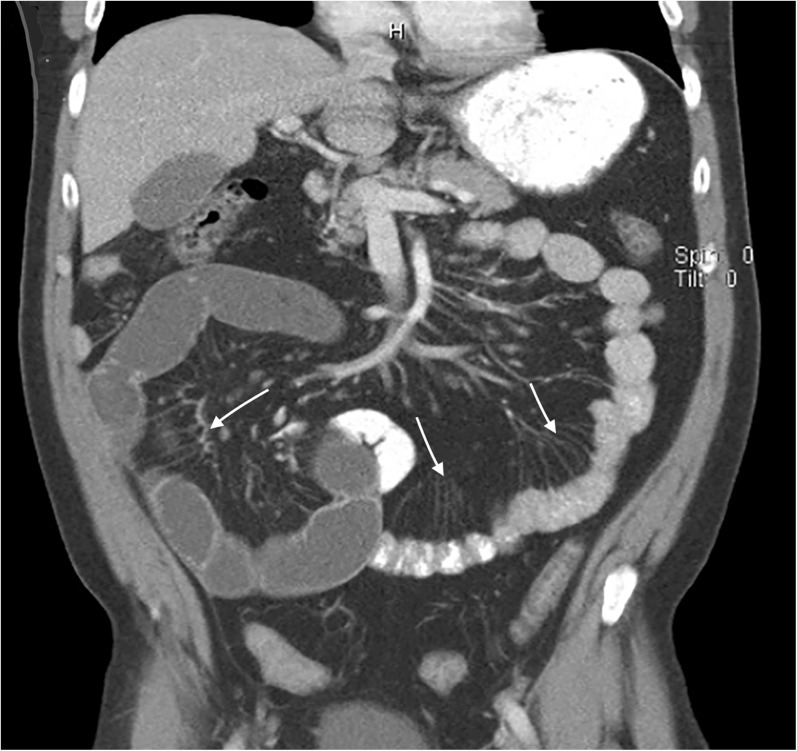

Fig. 1.

CT abdomen with contrast depicting the “comb sign,” characterized by hypervascularity of the mesentery with vascular dilation, tortuosity, and wide spacing of the vasa recta

A 43-year-old man presented with one day of crampy, diffuse abdominal pain associated with non-bilious, non-bloody vomiting. He reported similar episodes in the past that resolved spontaneously. Physical exam revealed epigastric tenderness. Initial white blood cell count was 13,700/mm3 and the serum C reactive protein was 1.76 mg/dL. Computed tomography (CT) of the abdomen showed a partial small bowel obstruction, ileitis, and the “comb sign” (Fig. 1). Colonoscopy revealed terminal ileal ulcers with luminal narrowing and stricture of the ileocecal valve (Fig. 2); pathology was consistent with Crohn’s ileocolitis.

Crohn’s disease is characterized by transmural inflammation of the bowel wall, most often involving the terminal ileum and proximal colon. Active disease has been associated with hypervascularity of the mesentery, including vascular dilatation, tortuosity, and wide spacing of the vasa recta that resemble the teeth of a comb.1 The comb sign is not pathognomonic for Crohn’s disease, and may be seen in vasculitis, mesenteric thromboembolism, and bowel strangulation.2 However, the presence of the comb sign may help identify acute inflammation in the patient with known Crohn’s disease and differentiate active Crohn’s from hypovascular diseases such as lymphoma.1 The patient’s symptoms resolved with steroid administration.